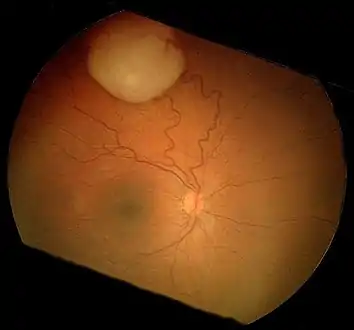

An ocular ultrasound of a large retinoblastoma tumor within the eye of a 3-year-old boy Funduscopic finding of a retinoblastoma

Funduscopic finding of a retinoblastoma Ocular fundus aspect of retinoblastoma

Ocular fundus aspect of retinoblastoma Large exophytic white tumor with foci of calcification producing total exudative retinal detachment

Large exophytic white tumor with foci of calcification producing total exudative retinal detachment Flexner-Wintersteiner rosettes in retinoblastoma